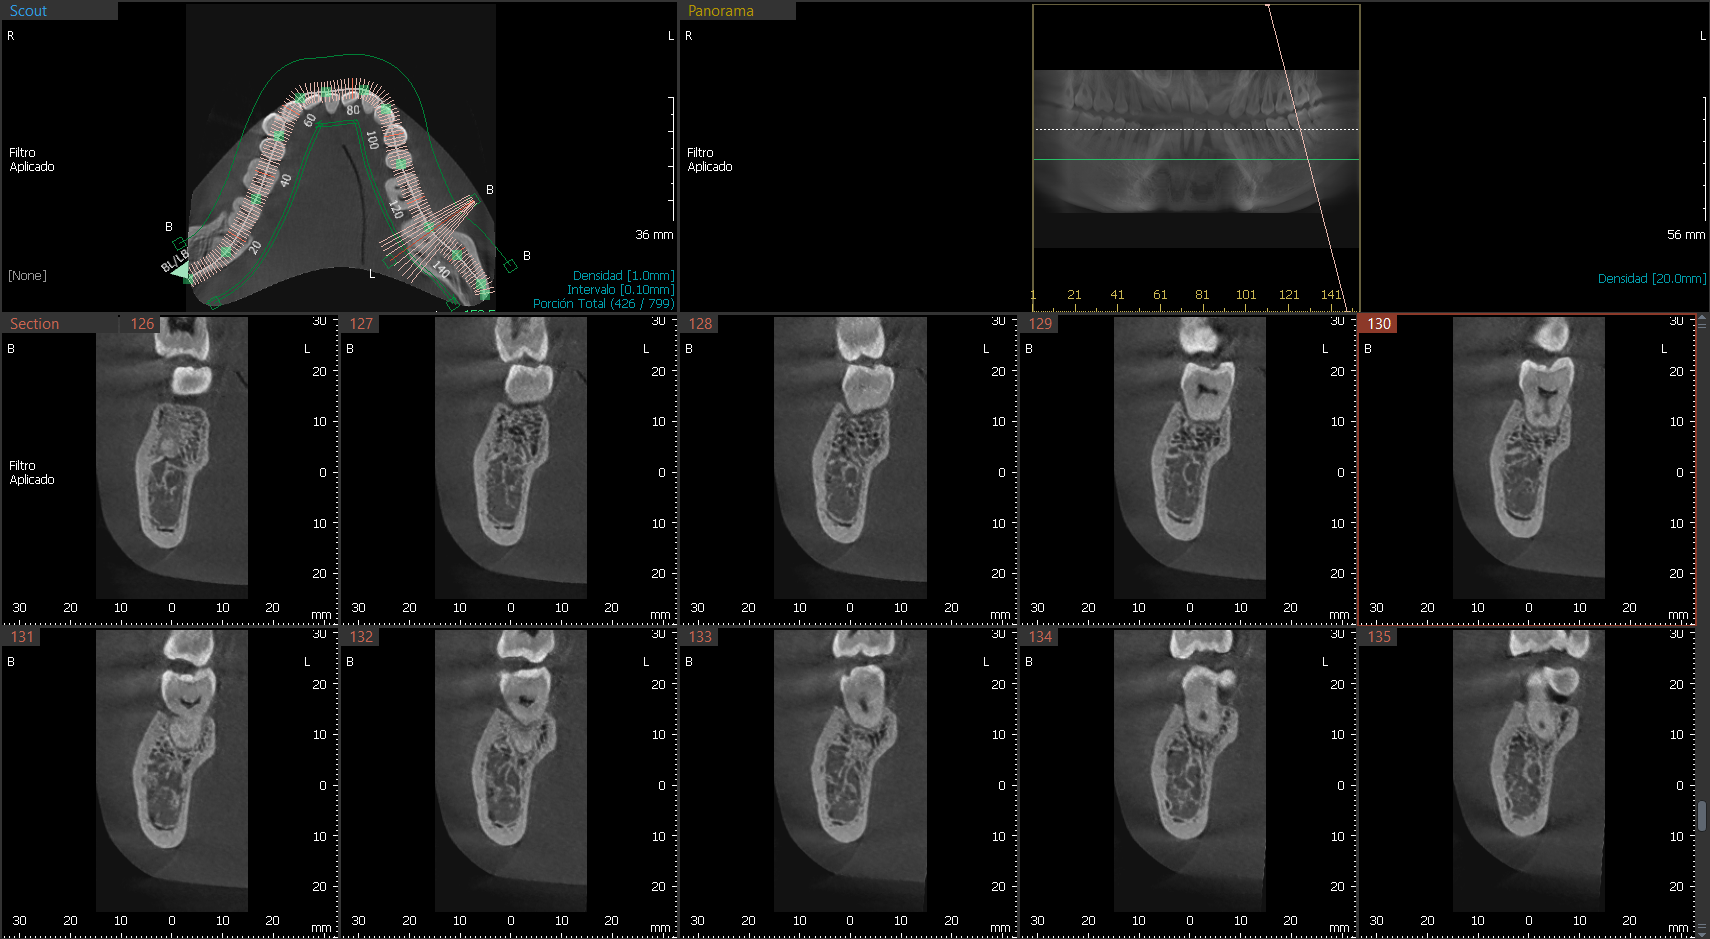

A9 cuenta con una tecnología lite que además de la función PANO + CEPH te permite obtener imágenes CT de manera lite para tu diagnóstico. Proporciona las imágenes más precisas y de mayor calidad.

Las imágenes 3D permiten realizar diagnósticos precisos para planificar los tratamientos dentales. Incluye la áreas maxilar y mandibular en una sola exposición. Ideal para cirugías de implantes y diagnósticos en cirugía oral.